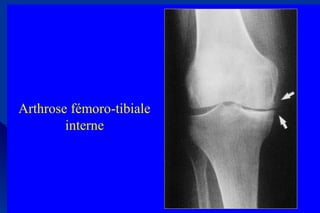

3/Arthrose fémoro-tibiale : signes radiologiques3/Arthrose fémoro-tibiale : signes radiologiques

• Clichées de face debout en extension, en semi-flexionClichées de face debout en extension, en semi-flexion

• Cliché de profil en semi flexionCliché de profil en semi flexion

Radiographies normales

Arthrose fémoro-tibiale

interne